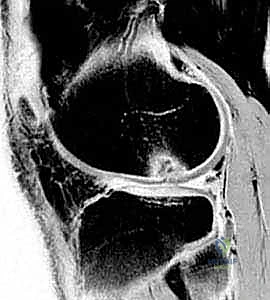

لفهم مرض التهاب العظم والغضروف السالخ، يجب أن نفهم أولاً تركيبة الركبة. يتغطى سطح العظام داخل المفصل بطبقة ناعمة ومرنة تُسمى الغضروف المفصلي (Articular Cartilage)، وتحت هذا الغضروف توجد طبقة من العظم تُسمى العظم تحت الغضروفي (Subchondral Bone).

في حالة الـ OCD، يحدث انقطاع أو ضعف في التروية الدموية (نقص الإمداد الدموي) لجزء معين من العظم تحت الغضروفي. نتيجة لهذا النقص في الدم، يبدأ هذا الجزء من العظم في التموت (Avascular Necrosis). وبما أن الغضروف الذي يعلوه يعتمد عليه في الدعم، فإن الغضروف يبدأ بالانفصال تدريجياً.

إذا تُركت الحالة دون علاج، يمكن أن ينفصل هذا الجزء من العظم والغضروف تماماً ليسبح داخل المفصل كـ "جسم حر" (Loose Body)، مما يؤدي إلى تدمير ميكانيكية الركبة وتآكل الغضاريف السليمة الأخرى.

- التصوير بالرنين المغناطيسي (MRI): هو "المعيار الذهبي" للتشخيص. بفضل خبرة الدكتور هطيف العميقة، يتم تحليل صور الرنين لتقييم صحة الغضروف، مدى انفصال القطعة العظمية، وحالة الأربطة المحيطة. الرنين يحدد ما إذا كانت الآفة مستقرة (يمكن علاجها بدون جراحة) أو غير مستقرة (تتطلب تدخلاً جراحياً).